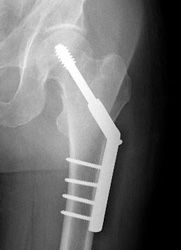

For true intracapsular hip fractures, the surgeon may decide either to fix the fracture with individual screws (percutaneous pinning) or a single larger screw that slides within the barrel of a plate. This compression hip screw will allow the fracture to become more stable by having the broken area impact on itself. Occasionally, a secondary screw may be added for stability.

The compression hip screw is fixed to the outer side of the bone with bone screws and has a large secondary screw (lag screw) that is placed through the plate into the neck and head of the hip (see compression hip screw figure above). The design of the device allows for impaction and compression at the fracture site. This may increase the stability of the area and promote healing.

Repair of an intracapsular fracture with a single compression hip screw.